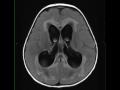

Medulloblastoma and Syrinx

4-year-old female with intractable nausea, vomiting, and severe papilledema. There is a large solid and cystic mass which arises from the roof of the fourth ventricle with inferior effacement and displacement. The mass restricts diffusion, extends through and enlarges the foramen of Luschka, and avidly enhances. There is moderate supratentorial hydrocephalus with a large syrinx in the mid to lower thoracic spinal region. The differential diagnosis includes brainstem glioma, ependymoma, and pilocytic astrocytoma, as well as medulloblastoma. The findings are most compatible with a medulloblastoma. Medulloblastomas are the second most common posterior fossa tumor in children. The typical presentation includes midline masses in the roof of the fourth ventricle with mass effect and hydrocephalus. Treatment is with surgical resection with adjuvant chemoradiation therapy.